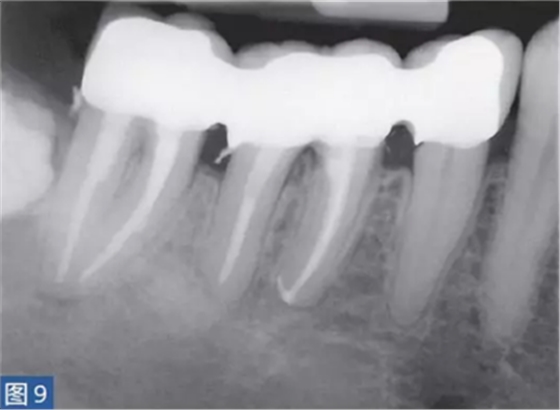

急性根尖膿腫(圖8 和9)是一種局部的或者彌漫性的液性病變。由壞死牙髓產(chǎn)生的微生物和非微生物刺激所引起的嚴(yán)重炎癥反應(yīng)造成了根尖周組織的破壞?;颊咄ǔ1憩F(xiàn)出中度至重度疼痛,根據(jù)嚴(yán)重程度還可能出現(xiàn)發(fā)熱和白細(xì)胞增多的全身癥狀。

臨床診斷顯示牙髓電活力測(cè)試結(jié)果陰性。叩診和觸診通常會(huì)引起疼痛。如果膿腫僅限于骨內(nèi),則不出現(xiàn)腫脹癥狀。放射學(xué)檢查,根尖周組織表現(xiàn)從無(wú)變化到發(fā)生明顯變化。

圖9:47 牙齒AAA。根管治療后?;颊咴谄浼彝パ泪t(yī)處做臨時(shí)義齒修復(fù)12 個(gè)月后的檢查。